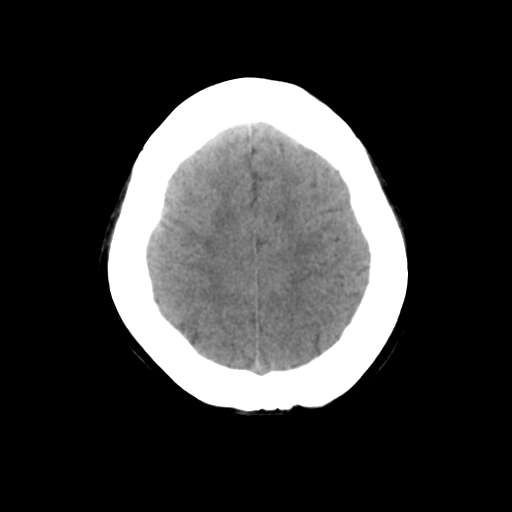

一台GE CT机突然出现下图伪影,请问是何原因?

并不是一直都有此伪影

这是设备原因造成的伪影一种伪影,

需要重新校准,

若不能矫正的话,那就没什么好办法了,

除非换配件

是不是原配球管啊,我院有台机器外圈有伪影是球管原因.

这种伪影一般还有个特点

在做薄层扫面时容易出现,一般是小于5mm,

但是在做常规10mm扫面时不会出现

这种现象并非一直出现,不分时间段,球管是租赁的,可能与电源有关

你有做一套的模和空气校正吗?没做好也会出这种情况的,一样是会有时好时坏的故障出的。